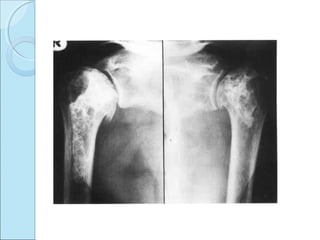

RADIOGRAPHIC FINDINGSRADIOGRAPHIC FINDINGS

 Juxta articular defects

transradiant subcortical band.

collapse of articular cortex.

sequestration of articular cortex.

secondary osteoarthritis.

 Neck and shaft lesions

dense areas.

irregular calcified areas.